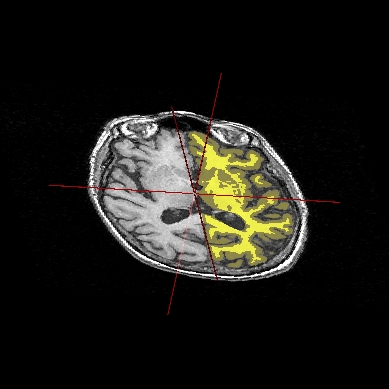

Application: Superimposing an anatomy and regions of interest (grey central nuclei)¶

In the following example, 3 objects are loaded in Anatomist:

Object1 (O1): anatomy

Object2 (O2): regions of interest graph drawn from the anatomy. So these 2 objects are in the same referential.

Object3 (O3): nomenclature to associate colors to regions of interest according to their name. This object does not have to be put in a window. Link between names in the nomenclature and in regions of interest is done automatically by Anatomist.

These 2 objects are in the same coordinates system, so they will be placed in the same referential, that is to say they will have the same color circle (red by default).